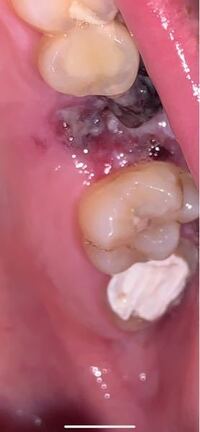

昨日上の歯の虫歯を抜歯したんですがこれはドライソケットでしょうか Yahoo 知恵袋